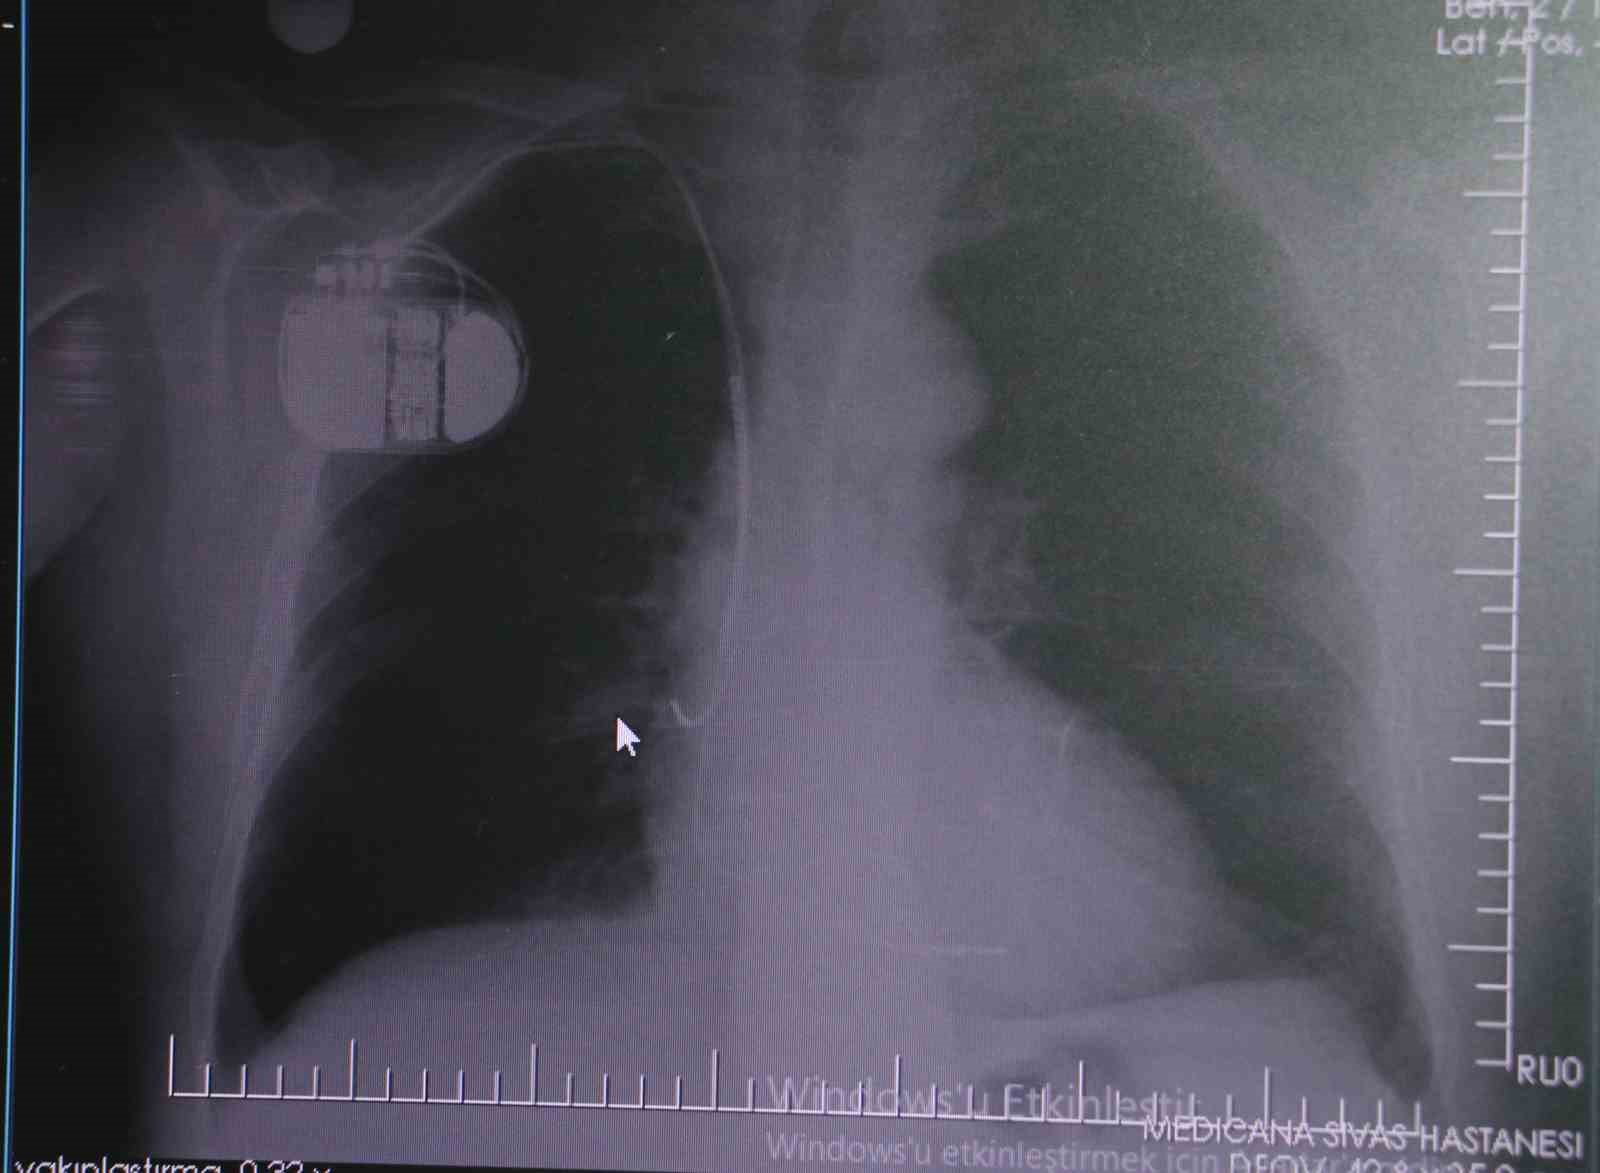

Kalp krizleri sonrası kalp dokusunun zarar gördüğünü söyleyen İsmail Erdoğu, "Dünyada artık kalp hastalıkları en sık ölüm sebeplerinden biri. Kalp hastalıklarında çok fazla grup var. Biz kalp hastalıkları deyince sadece kalbinde stent olan ve damarlarında sorun bulunan insanlardan bahsetmiyoruz. Aynı zamanda tansiyon ve şeker hastaları da kalp hastalıklarına aday. Toplumun yaklaşık yüzde 30-35’lik bir kısmını kapsıyoruz. Çok yaygın bir hastalık ve bu hastalıkta teknolojik kapsamda, ilaç konusunda son 30 yılda çok ciddi gelişmeler oldu. Geçmişte insanları hastanelerde kalp krizinden dolayı kaybederken şimdi hastaneye başvurular sonrasında yaşama tutunmak büyük oranda mümkün. Yaşanan ölümler ise genellikle hastaneye gelmeden önce gerçekleşmekte. Kalp krizinden kurtulmanın hastalarda belli bir bedeli oluyor. Kalp krizi sonrası kalpteki dokular zarar görüyor ve kalp yetersizliği oluşuyor. Bu kalp yetersizliği olan kalplerde ritim bozuklukları ve ani ölümler gibi sorunlar gündeme gelebiliyor. Bunlardan uzun vadede korunmak için hastalarda mutlaka bir kalp piline ihtiyaç duyuluyor" dedi.

Kalp pilleri ile MR cihazına girilebileceğini belirten Erdoğu, "Çok büyük bir ameliyat değil ama yine de ciddi bir cerrahi işlem. Kalp pili, tıpta son 30 yılda yaşanan gelişmelerden en büyüğü. Bir bilgisayarın küçültülüp insan vücuduna konulmuş hali aslında. İnsan ömrünü ciddi oranda uzatan bir tedavi. İnsanlar bir şokla hayata tutunurken, pil olmasaydı öleceğini düşündüğümüz birçok hastamız var. Kalp pilinin bu özelliği, uygun hastalarda ciddi oranda ani ölümü engelliyor. Hastanın başına gelecek bir kalp durması durumunda yanında bir sağlıkçı yoksa, onun ritmini düzeltecek defibrilatör cihazı yoksa hastayı hayatta tutmak mümkün değil. Uygun endikasyonlarda kalp pili olduğu zaman, pil hastaların ritmini algılıyor ve acilde yapılan şoklamayı yaparak hastayı hayata döndürüyor. Kalp pillerinde yeni teknolojilerle MR’a girmek mümkün, tomografiye zaten girebiliyorlar. Tarama cihazlarından geçmelerini uygun görmüyoruz. Bu tarz durumlarda hastalarımız ’kalp pilim var’ dediğinde muaf tutuluyorlar. Kalp pilleri ciddi teknolojik cihazlardır. Vücudun içindeki titreşimi, örneğin mikser kullanmak, kolunu sallayacak herhangi bir eylem kalp pilinde olumsuz etki oluşturabilir. Soğuk havalarda vücutta oluşan ciddi titremeler kalp pilinin hafızasını karıştırıp kalbin durduğunu düşündürebilir ve gereksiz şoklama yapabilir. Bu tarz kişilerin soğuk havalarda daha temkinli olması gerekir" diye konuştu.